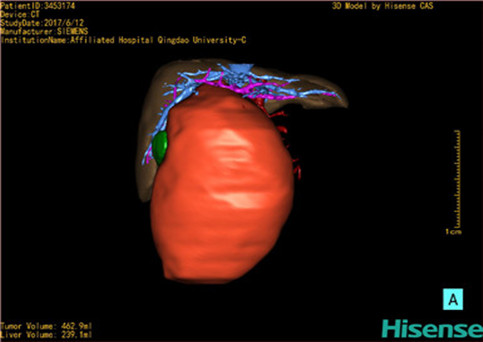

近年来由于数字医学的发展,基于可视化三维重建技术的计算机辅助手术系统极大推进了小儿肝脏肿瘤的精准手术的进步。可以立体透视肝脏解剖、精确掌握肝段的边界、精确测算肝段乃至任意血管所支配的功能体积、准确定位病灶及其与邻近血管的解剖关系,最终对不同手术方案进行比较、筛选和优化。因此,计算机辅助手术规划系统是实现精准肝切除的有力辅助工具,是未来数字外科、精准外科等21世纪外科新理念的重要技术支撑。

计算机辅助手术规划系统具有良好的操作可行性、计算准确性和三维显示效果,可半透明、交互式显示真实的肝内立体解剖关系和空间管道变异,准确计算肝内管道的直径、走行角度,两点间的垂直距离,和任意血管的支配或引流范围等传统二维影像无法获取的信息,有助于实施个体化手术,提高了手术的确定性、预见性和可控性。计算机辅助手术规划系统可直观显示预留肝脏的结构和功能,并可通过虚拟切割功能辅助术者对手术方案进行蹄选和优化,系统评估手术风险和制定对策,改变了部分二维规划的术式和切除范围,使部分二维规划认为不能切除的患者成功手术,提高了手术的根治性、安全性和病变的可切除性,更加符合精准肝脏外科的术前规划要求。详见第11章。

随着计算机技术及影像检查技术的不断发展,以精确的术前影像学和功能评估、精细的手术操作为核心的精准肝切除技术日益受到重视。基于数字医学的计算机辅助手术技术(computer-assisted surgery,CAS)则是实现肝脏精准手术操作的基础。计算机辅助手术系统(CAS)可将术前二维(two dimensional,2D)的CT/MRI影像数据进行三维(three dimensional,3D)重建,建立个体化的肝脏三维解剖模型,清晰显示肝脏内脉管系统的走行及解剖关系,还原病灶与其周围脉管结构的立体解剖构象,准确地对病变进行定位、定性和评估,制定合理、定量的手术方案,实施个体化的肝脏血管取舍分配方案及实施精准肝脏手术。一般认为CAS包括:创建虚拟的患者的图像;患者图像的分析与深度处理;诊断、手术前规划、手术步骤的模拟;术中实时导航。应用本技术后,由于可以更清晰地看出肿瘤的界限,特别是根据肝血管的显影,判断出肿瘤与门静脉及肝静脉的关系以在手术前较准确地估计出手术成功切除的可行性。以往部分根据普通强化CT判断无法手术的病例而被评估为可以成功切除并手术成功。